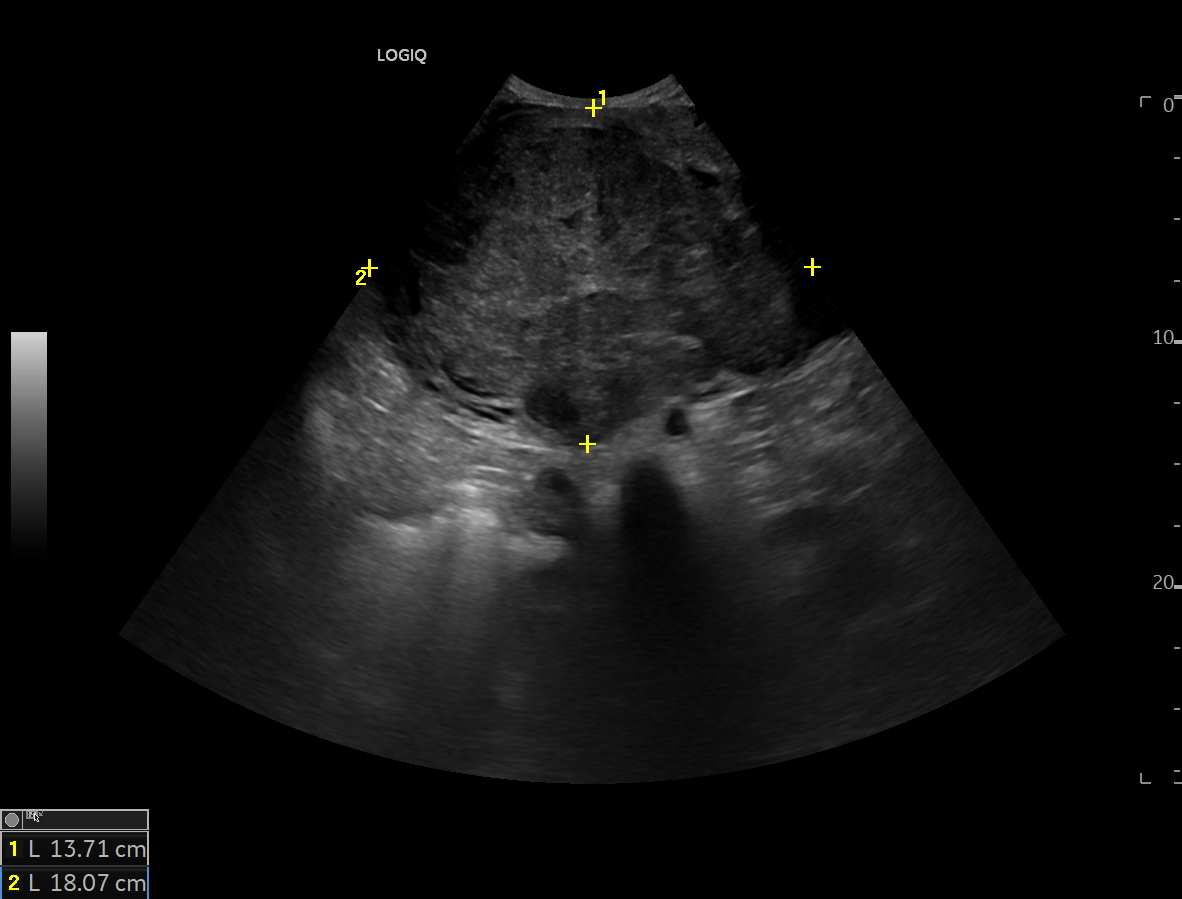

Se realiza ecografía clínica, en la cual se encuentra masa abdominal de 20x20 cm.

Se realiza ecografía clínica donde se aprecia masa abdominal de 20x20 cm sin identificar origen, porque posteriormente se solicita interconsulta con ginecología, la cual le realiza RMN, la cual da el siguiente resultado:

Masa hipogástrica compatible con leiomioma uterino, con focos de degeneración quístico-necrótica e hialina.